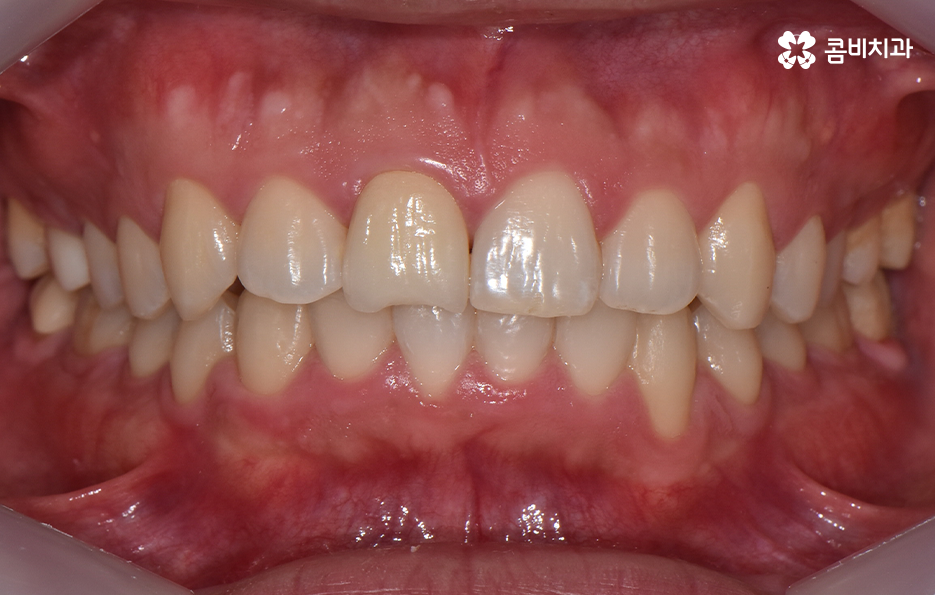

오늘은 아랫니만 교정을 한 사례를 통해서 이와 같은 고민을 하는 분들에게 도움이 될 만한 치아교정 정보를 알아보려고 하고 있어요

하지만 위에 보시는 환자분의 사례는 윗니와 아랫니의 교합을 고려하고 얼굴형, 골격 등을 고려했을 때도 아랫니만 교정이 가능했던 사례인데 일반적으로 윗니가 아랫니를 살짝 덮고 있어야 하는데 아랫니의 앞니 부분이 유독 안으로 들어와 있었기 때문에 아랫니교정 만으로도 치아교정이 가능했던 사례라고 보시면 좋을 거예요

위 환자분의 사례로 보면 아랫니 중에 하나가 유독 앞으로 튀어나와 있고 나머지 치아는 안으로 들어가 있기 때문에 교합으로 따져볼 때는 아랫니를 전체적으로 앞으로 이동시켜야 했기 때문에 비발치로도 충분히 교정이 가능했고 아랫니교정 만으로도 치료가 가능했어요